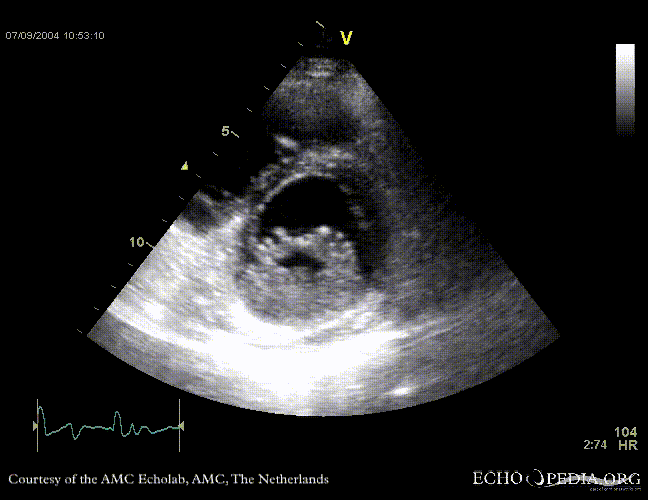

Case 11

| Courtesy of: J. Vleugels, AMC, The Netherlands | |

| <flash>file=E00152.swf | <flash>file=E00153.swf |

| Sarcoidose 7 | Sarcoidose 8 |